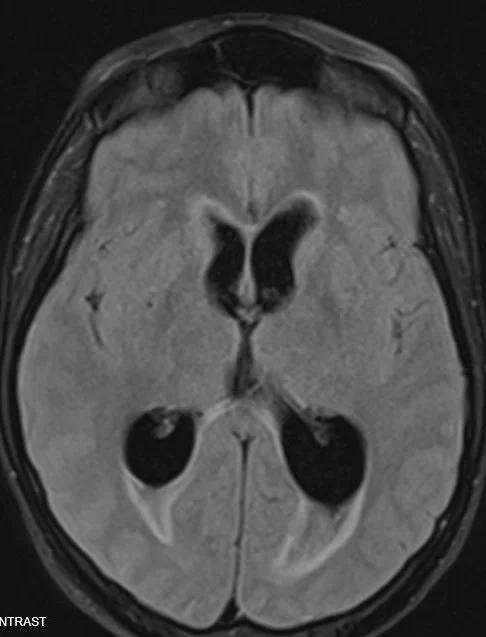

what does it show on the T2 weighted image?

Our patient had post traumatic hydrocephalus.  This was originally described in 1914 when Dandy discussed a case of hydrocephalus in a young boy with a severe fall some time earlier..  Ventricular dilatation occurs regularly after severe head injury with an incidence of from 29-72%.    On CT the anterior horns of the lateral ventricles are dilated.  There is transependymal flow as shown below; this means the pressure in the CSF is so high it actually starts to move backwards into the brain.

The arrows point to transependymal flow on MRI caused by increased csf pressure